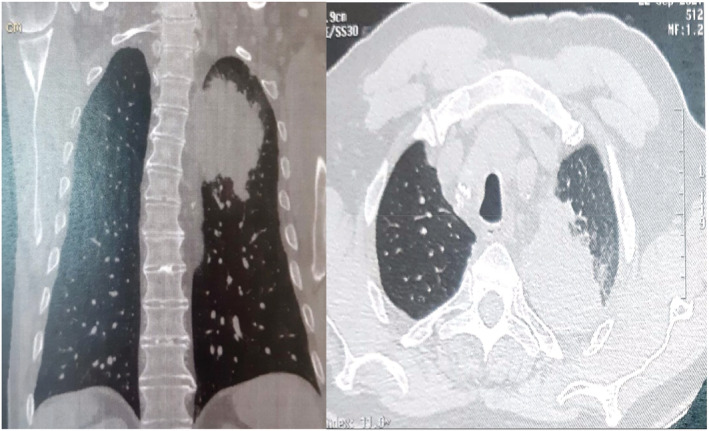

The second patient is a 76‐year‐old smoker man with a history of coronary disease treated by a coronary artery bypass surgery. He had an adenosquamous carcinoma of the lung in first stage (T1N0M0) (Figure 3). Surgery was not possible in front of his hurt disease. He was treated with exclusive radiotherapy. Six months later, the patient presented dry cough, dyspnea, asthenia, and urinary incontinence. He also noticed a sudden appearance of multiple eruptive seborrheic keratoses on his back (Figure 4). Full body CT scan demonstrated large left upper lobar mass which engulfs the left pulmonary artery, invades the hilum, left stem branch up to the carina with multiple hilar and mediastinal lymph nodes (Figure 5) and the appearance of lever, pulmonary, and sacrum metastases. Overall, the findings were compatible with the diagnosis of progressive tumor disease. The appearance of LTS coincides in this case with the tumor progression.

FIGURE 5.

CT scan of the chest demonstrated large left upper lobar mass which engulfs the left pulmonary artery, invades the hilum, left stem branch up to the carina with multiple hilar and mediastinal lymph nodes